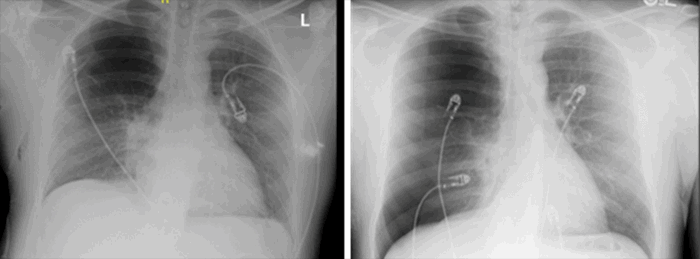

Figure 2. Before And After Chest Tube Removal. Published with Permission

A 29-year-old male presented with acute mid-sternal chest pain associated with dyspnea that was precipitated by a cough after taking “a big hit on his vape,” as indicated by the patient. His past medical history was significant for a diagnosis of asthma and smoking cigarettes and marijuana. He formerly smoked cigarettes at the age of 18 and switched to vaping at the age of 21. He reported a three-pack per year smoking habit for his entire life. On presentation, he was hemodynamically stable despite a large, right-sided pneumothorax found on a chest radiograph (CXR). A right-sided chest tube was immediately placed without any complications. Subsequent computed tomography (CT) scan of the chest demonstrated multiple right upper lobe bullae with one large apical bulla (Figure 1A-D). Notably, the left lobe was free of bullae. After 24 hours on water seal, the chest tube was removed after the morning CXR demonstrated resolution of the pneumothorax. Upon repeat CXR (Figure 2), a recurrence of the right-sided pneumothorax was noted. Interventional radiology was consulted for the placement of a pigtail pleural catheter.